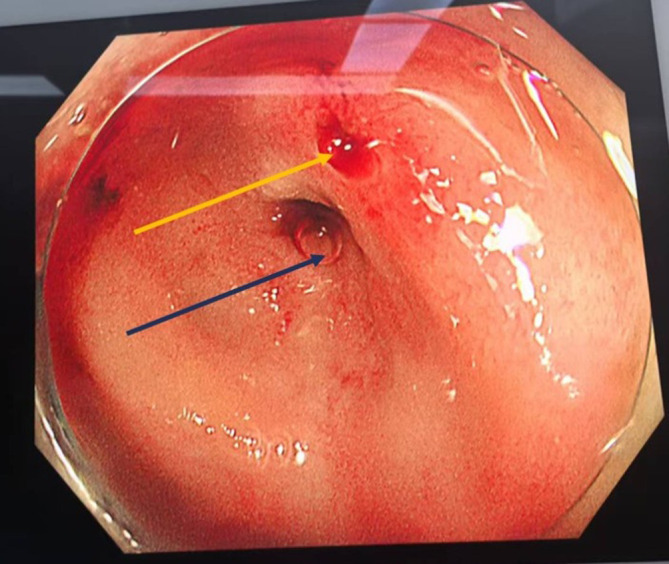

Meckel's diverticulum is one of the most common congenital anomalies of the gastrointestinal tract in pediatric populations worldwide. Although Meckel's diverticulum itself is usually asymptomatic, patients often present with complications such as gastrointestinal bleeding, Meckel's diverticulitis, intestinal perforation, and other associated symptoms. Notably, Meckel's diverticulum is relatively uncommon in adults, with cases complicated by acute massive gastrointestinal bleeding being particularly rare. We report the case of a 41-year-old man presenting with hematochezia for one day. Upon admission, his hemoglobin level dropped significantly from 98 g/L to 62 g/L within 24 hours. Contrast-enhanced computed tomography strongly suggested contrast media extravasation, indicating active bleeding. Subsequent gastrointestinal endoscopy, including colonoscopy, failed to identify obvious pathological findings. Mesenteric angiography successfully localized the bleeding vessels, but multiple embolization attempts were unsuccessful. The initial imaging and endoscopic modalities may not pinpoint the source of bleeding in this rare condition. Ultimately, a combined laparoscopic and endoscopic approach was employed, which successfully identified and localized the bleeding site in the Meckel's diverticulum. Laparoscopic intestinal resection was then performed, and postoperative pathological examination confirmed Meckel's diverticulum with ectopic gastric tissue. Meckel's diverticulum-induced bleeding in adults is severe yet rare, with nonspecific diagnostic features that often complicate timely identification. In managing the case of massive gastrointestinal hemorrhage, we achieved a successful outcome through combined laparoscopic intestinal resection and endoscopic surgery, with timely diagnosis and targeted intervention leading to complete recovery. This case underscores the critical role of a multimodal diagnostic and therapeutic strategy, particularly the integration of laparoscopy and endoscopy, in overcoming the challenges of nonspecific presentations. It serves as a valuable reference for clinicians, emphasizing that persistent diagnostic uncertainty in severe lower gastrointestinal bleeding should prompt consideration of rare etiologies like Meckel's diverticulum, and that a combined surgical-endoscopic approach can be pivotal in achieving definitive diagnosis and curative treatment.